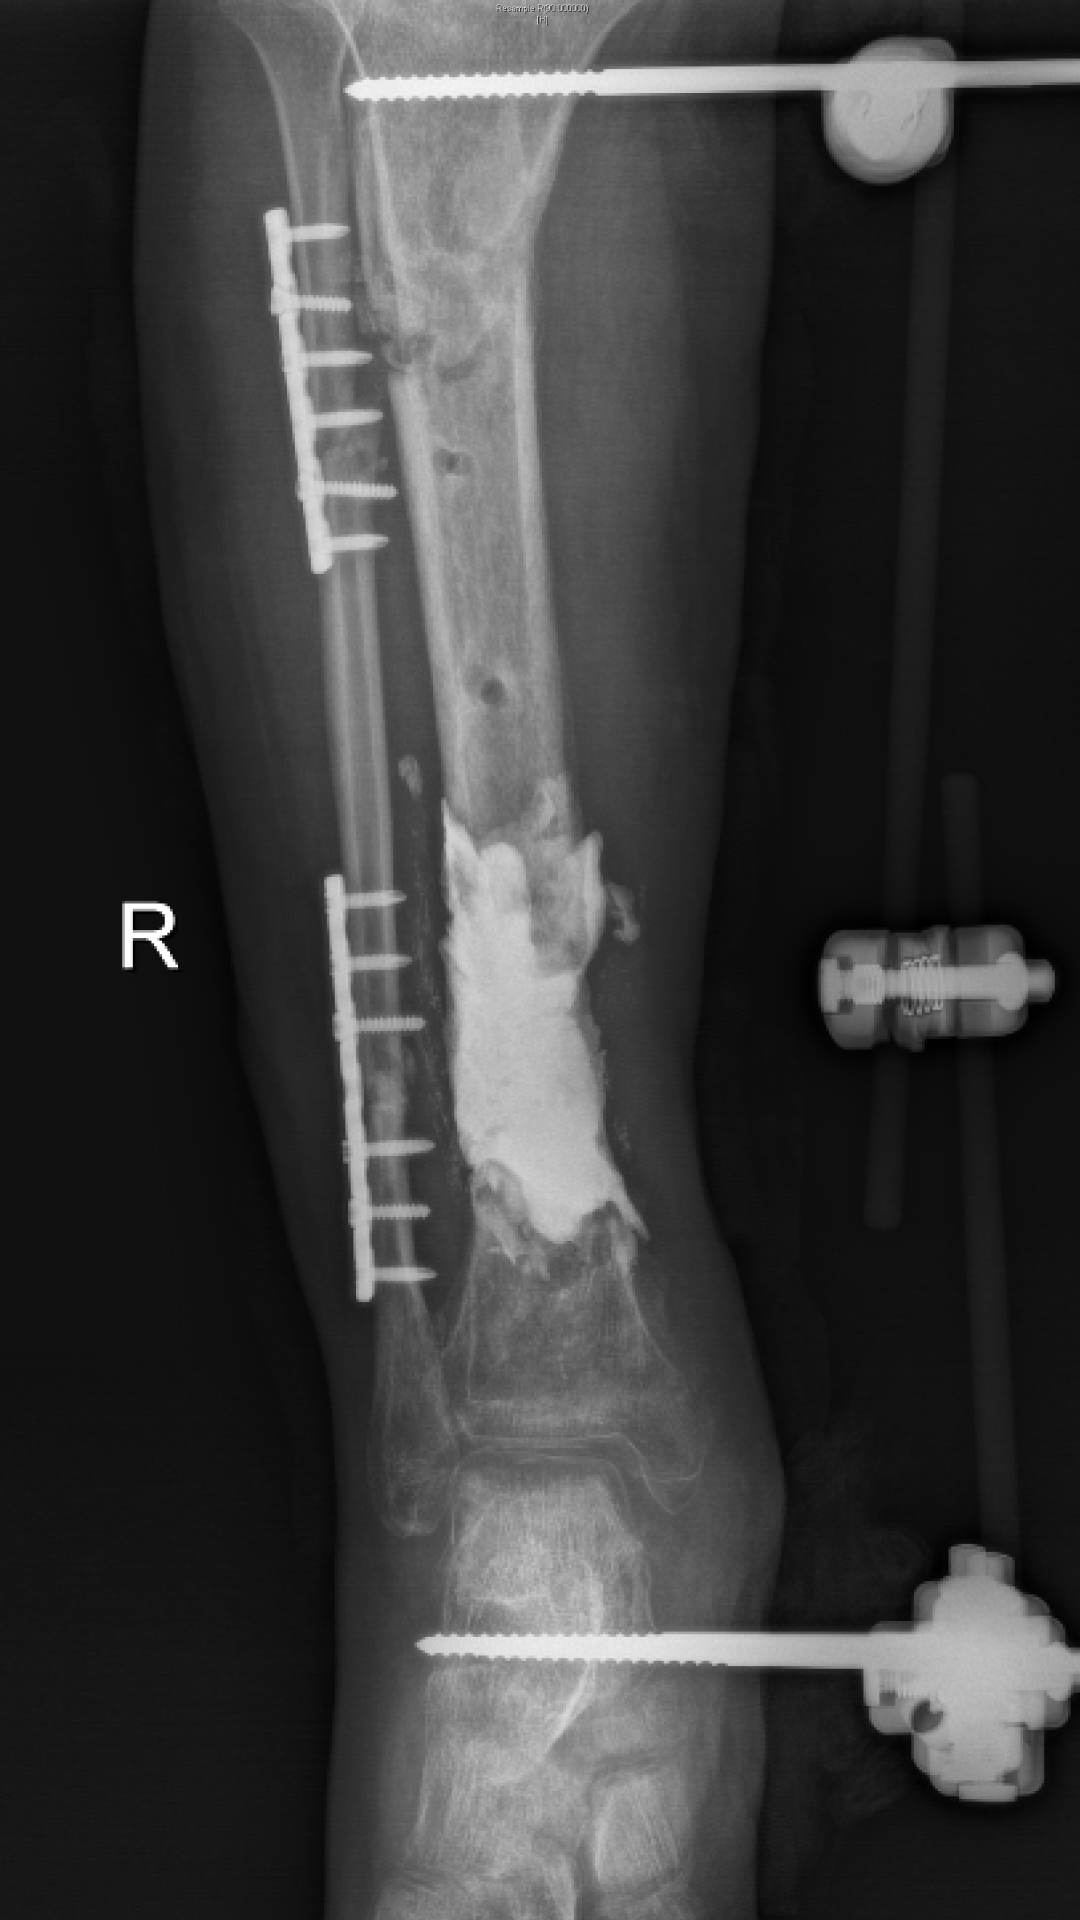

1、骨水泥植入

徐杨主任医师介绍,对于肢体毁损伤后期合并感染患者,保肢最大的难题是清创及骨与软组织重建,masquelet技术能够形成骨水泥诱导膜,不但能起到屏障作用,还含大量微血管,丰富血供,并能分泌各种促骨生长因子,具有成骨快、愈合率高的优点。尤其适合治疗长节段、严重感染性骨缺损病例。